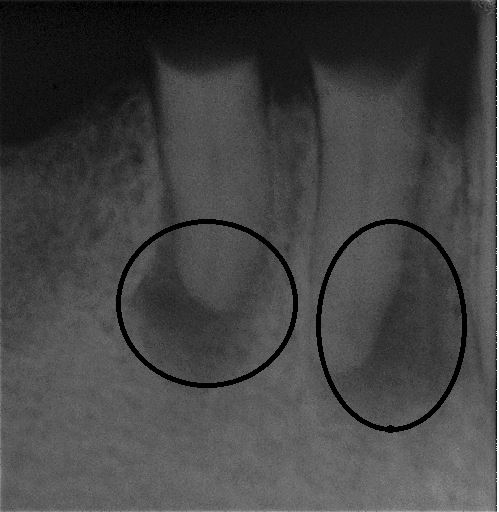

Fallbeispiel für einen Seitenrand

Da die Wurzelkanäle sehr klein sind und sich oft verzweigen, ist es nicht immer einfach, alle Kanäle mit ihren Seitenästen aufzufinden.

Bei der modernen endodontischen Behandlung können durch ein Dentalmikroskop auch kleinere Kanälchen aufbereitet werden, die man auch mit einer Lupenbrille nicht finden würde.

Nur wenn das Wurzelkanalsystem komplett aufgefunden und gereinigt wird, hat eine Wurzelkanalfüllung eine gute Langzeitprognose.